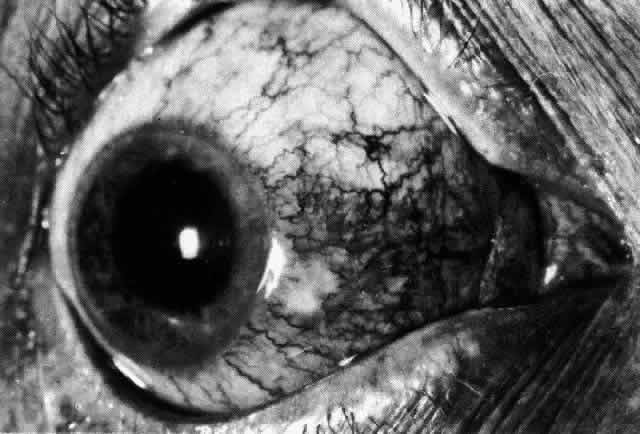

The inflammation of the eye is a prominent feature. The inflammation has a bluish-red hue in contrast to the brighter red of episcleritis and may be sectorial or diffuse. The severity of inflammation seems to depend on the amount of episcleral tissue present. Therefore, it is more prominent in younger people and is least prominent in those with rheumatoid arthritis in whom the episcleral tissue almost disappears. Each of the various types of scleritis can be distinguished by its typical clinical appearance. Because the pathologic change is in the sclera, there is always edema and/or necrosis of that tissue. This gives rise to an overlying episcleral edema and to congestion that may be very severe and may need blanching with epinephrine 1:1000 or phenylephrine 10% to detect the underlying edema. The sclera that is edematous is pushed forward, and the deep episcleral network is more congested than the superficial networks (Figs. 27 and 28). It is usually easy to ascertain by simple observation that the patient has scleritis and not episcleritis. However, it is not as easy to ascertain whether the patient has early necrotizing scleritis. It is in these patients that fluorescein angiography has considerable value, because the first changes are detectable in the ocular vasculature. Prompt and adequate treatment can prevent these changes from becoming irreversible.

Diffuse Anterior Scleritis Diffuse anterior scleritis is the most common and least severe type of scleritis. The inflammation is widespread, and it may involve either a small segment or the whole of the anterior segment, sometimes with such severe overlying inflammation as to justify the name “brawny” scleritis (Fig. 29). On slit lamp examination, the vascular pattern of both deep and superficial layers may be distorted, so that the normal radial pattern of the vessels is lost; large anastomotic channels develop, leading to beading and tortuosity of the remaining vessels (Figs. 30 and 31; Color Plate 1C).